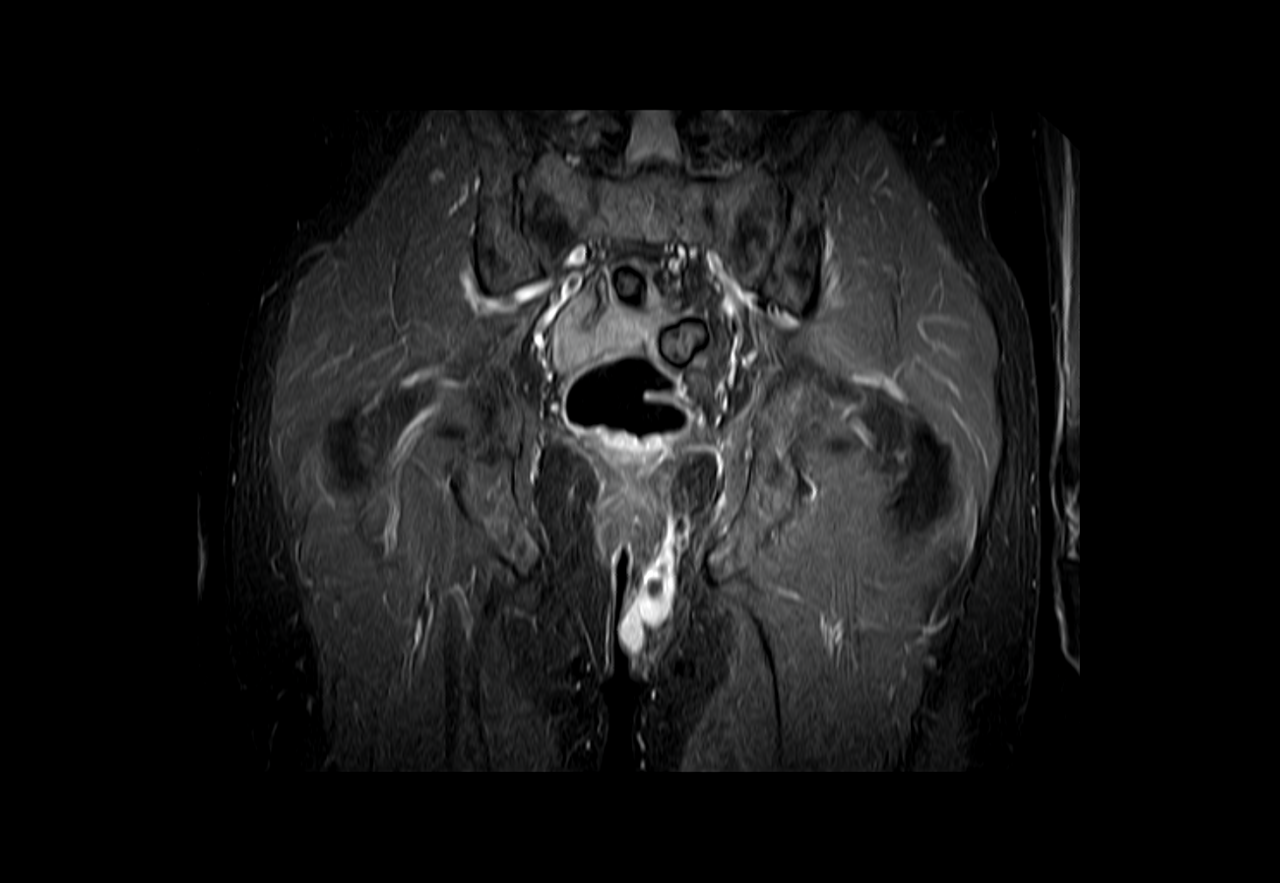

Trotzdem hatte ich mich dann bei meinem Schwimmtrainer nach der Vereinsempfehlung eines Orthopäden erkundigt und dort umgehend einen Termin gemacht. Dieser hat dann auch erst mal eine umfassende Untersuchung aller potentiellen Ursachen vorgeschlagen, statt direkt mit einem Medikamenten Rezept, Spritzen oder Physiotherapie um die Ecke zu kommen. Er hat dann alle Gelenke und Muskelbereiche abgetastet, um mich danach zum umfassenden Röntgen zu schicken. Hier durfte ich dann in x Ballettpositionen vor der Röhre stehen, um die Gelenke aus allen erdenklichen Positionen abzulichten. Zu guter Letzt musste ich noch einen separaten Termin für eine MRT Untersuchung machen, welchen ich Glücklicherweise dann sehr schnell bekam. Nach einer gefühlten Ewigkeit in der Röhre wurde ich dann zur Besprechung des Ergebnisses von der Ärztin hereingerufen. Diese offenbarte mir dann direkt, dass es sich tendenziell eher nicht um ein orthopädisches Problem handelt, was die Schmerzen verursachten. Auf dem Bildschirm zeigte Sie mir auf der linken Seite von meinem Hintern zwischen dem ganzen Grau eine riesige weiße Stelle. "Das gehört hier nicht hin" und ist eine große flüssige Entzündung, konkreter ein eitriger Abszess. Den Begriff Abszess hatte ich schon einmal gehört, konnte aber nicht wirklich einsortieren, was es damit auf sich hatte. Die MRT-Ärztin wollte dem Kollegen der Orthopädie nicht zuvor kommen, sagte mir aber gleich, dass hier ein Proktologe eher die richtige Wahl wäre. Ein Prokto-was? Nach der Befragung des Orakels Googel fand ich heraus, dass ein Proktologe quasi das Gegenteil eines Zahnarztes ist, was der Zahnarzt für den Mund, ist der Proktologe der Fachmann für das andere Ende der Körperöffnungen... Also fix einen Termin machen und hoffen das er schnell helfen kann. Doch da war ich wohl etwas zu optimistisch.